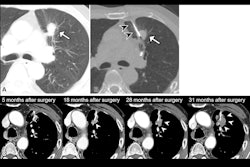

CT-guided percutaneous needle biopsy is a minimally invasive procedure used to analyze tissue and is key in diagnosing suspicious pulmonary nodules, the authors explained. The accuracy of the procedure alone for identifying malignant tumors varies between 64% and 97%, and this is thought to be due to different levels of metabolic activity in the tumors, they added.

F-18 FDG-PET/CT is a molecular imaging approach that can locate maximum metabolic activity regions in tumors based on glucose metabolism by cancer cells. Yet there is no set guideline recommending PET/CT scans before CT-guided lung biopsy to assess the best site for obtaining tissue, the authors noted.